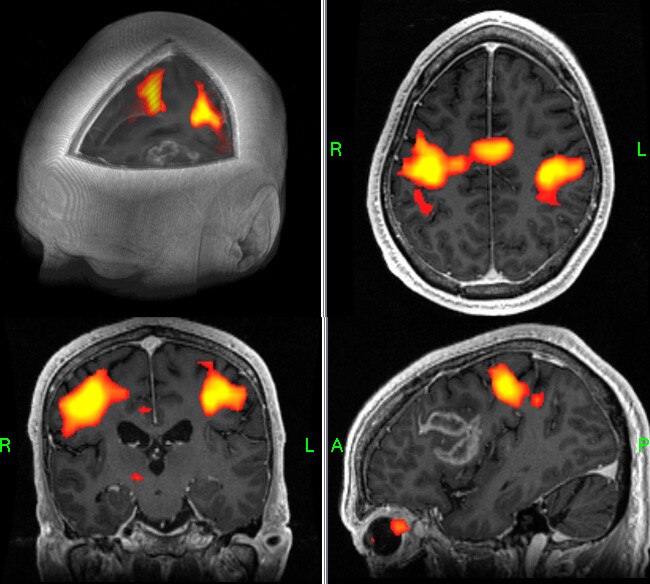

- View functional data overlaid on the structural image in 2D or 3D renderings. Add annotations or change color and opacities.